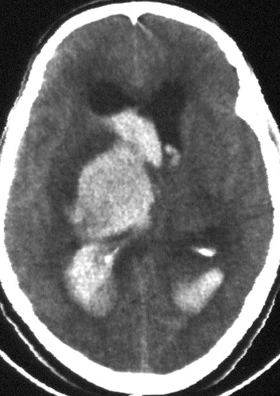

A. Imaging study. *CT head *(without contrast; axial plane)

B. What is the most likely diagnosis? Subarachnoid hemorrhage

- Multiple areas of high attenuation in the basal cisterns, Sylvian fissures, and sulci are

- characteristic of extensive subarachnoid hemorrhage.

Intra ventricular hemorrhage

- Anterior/Posterior Horns hemorrhages

- 3rd ventricles